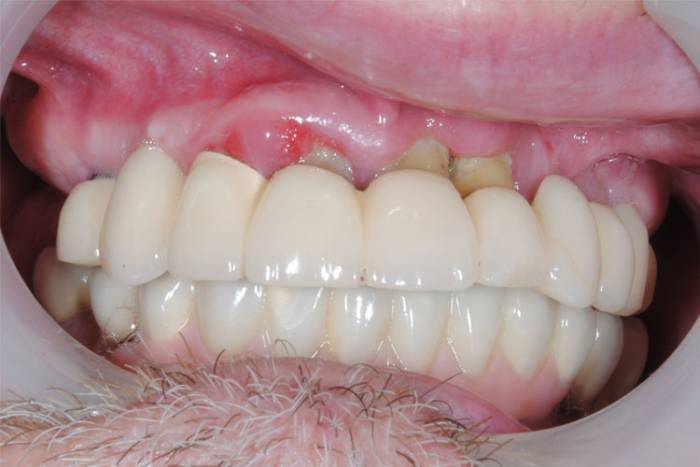

- гиперемия (покраснение) десны в проекции имплантата;

- воспалительная отечность мягких тканей;

- формирование патологического зубодесневого кармана;

- выделение крови или гноя.